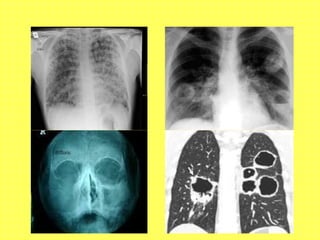

• Chest X ray / HRCT thorax:

-Pulmonary infiltrates- small vessel vasculitis

-Pulmonary cavities- Wegener’s granulomatosis

• Xray Para Nasal Sinuses

-Sinusitis of Wegener’s

Wegener’s Granulomatosis • Classicaltriad  URT + LRT + renal • Chronis sinusitis, Pulmonary nodules, Pulmonary cavities, Rapidly Progressive Glomerulonephritis • Cutaneous vasculitis, Eye lesions may be present • Non specific symptoms may predominate